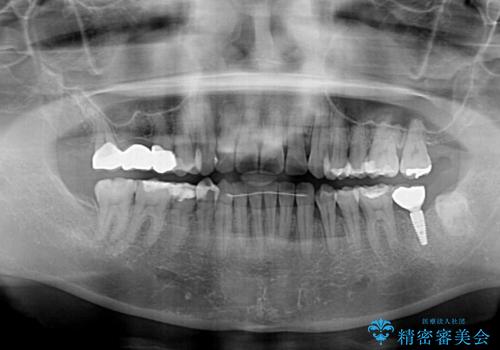

- 上下奥歯の欠損を気にして来院された患者様です。

以前矯正した後戻りにより前歯に叢生が認められたため、矯正治療の提案をしたところ、補綴治療と合わせて矯正治療を行うこととしました。

下顎欠損部はインプラントにて、上顎中間欠損部はブリッジによる補綴治療を行い、他にも気になっている銀歯をセラミックインレーやゴールドインレーにて修復治療を行うこととしました。

後戻りの程度は軽度であったため、インビザライン・ライトを用いて歯列を整えました。

再度後戻りするリスクを最小限に食い止めるため、下顎前歯の舌側を細いワイヤーで固定しました。